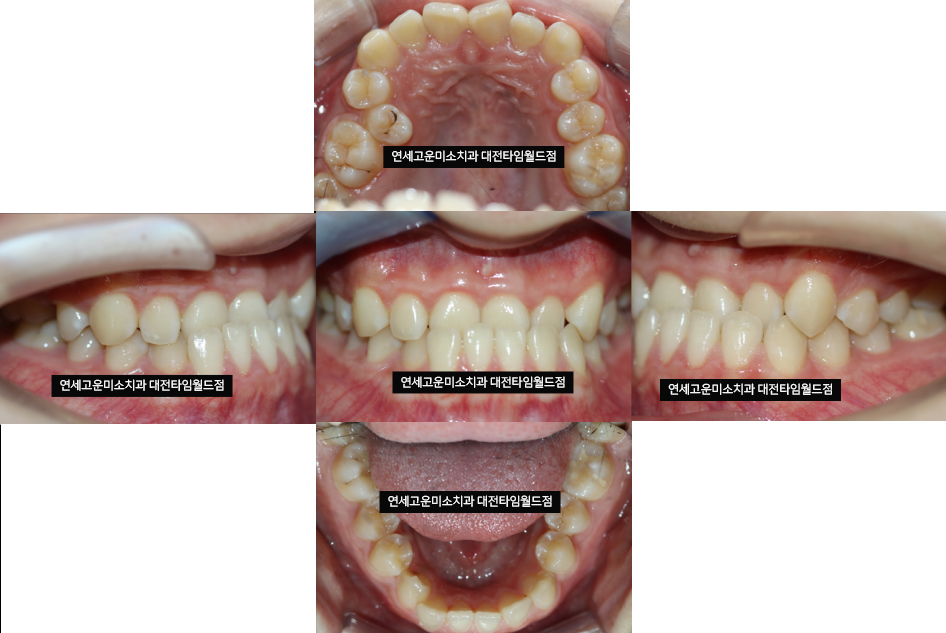

10대 여자 환자분이시고요

아래턱이 살짝 나와 보이고

치아가 거꾸로 물리는

반대교합을 주소로 내원하셨습니다.

- 양악 수술 없이 반대교합 해결이 가능할까요?

- "첫 번째 확인해야 할 사항" 은

윗니랑 아랫니 앞니끼리

닿게 유도할 수 있는지 확인해 보세요

만약 앞니끼리 닿을 수 있는 분들은 교정으로

해결이 가능한 경우가 많습니다.